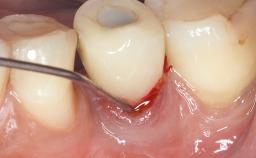

A 79-year-old female patient was referred to the Department of Periodontology of the University of Bern, Switzerland by her private dentist in May 2019. She had been rehabilitated in May 2005 with two tissue-level implants (Institut Straumann AG, Basel Switzerland) at sites 13 and 15, supporting a three-unit cemented fixed dental prosthesis (FDP). The metal-ceramic FDP had been cemented permanently with a glass-ionomer cement (Ketac Cem; 3M ESPE, Seefeld, Germany). Implant 13 had been diagnosed with peri-implant mucositis by the referring dentist in the course of regular supportive therapy. The patient was in good general health, did not smoke, and exhibited good self-performed plaque control.